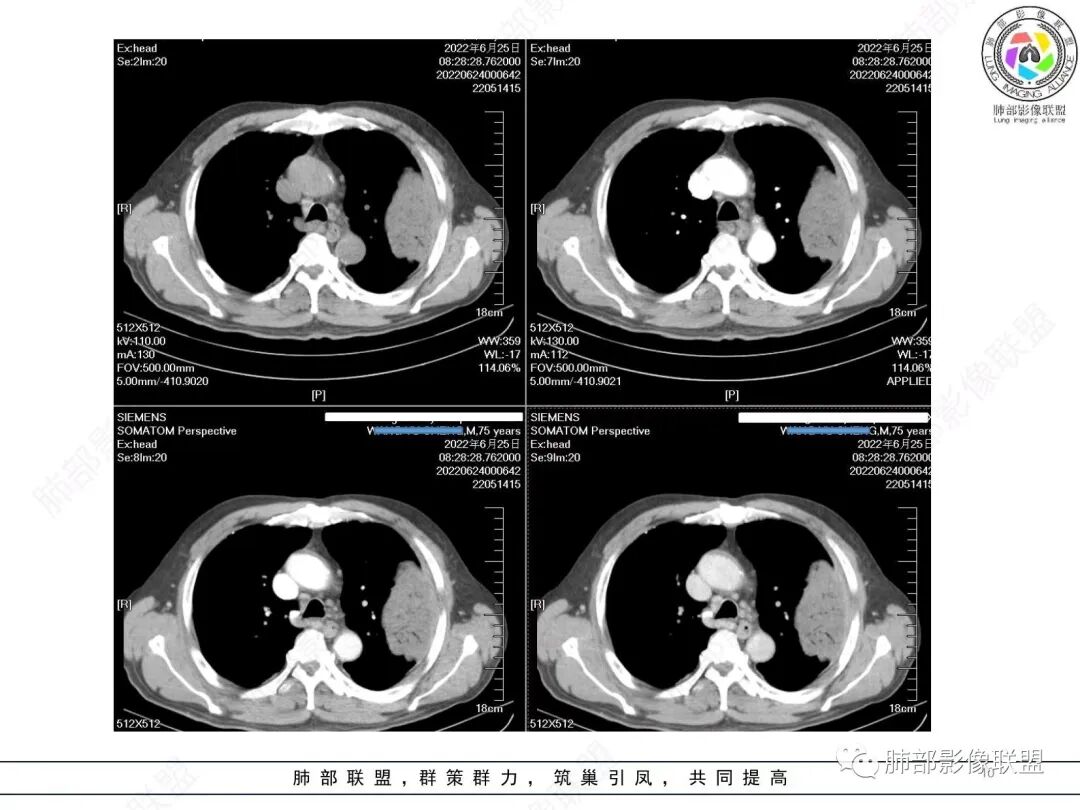

谢加平:

左肺上叶大肿块,膨胀性生长,边界清,密度较低,见部分坏死区,强化弱,肿块见支气管充气V扩张征,分布僵直,枯树枝特点,另一个重要特点血管造影征,淋巴瘤,肿块长轴与胸膜平行,与隐球菌鉴别,隐球荚膜抗原检查,明确诊断经皮肺穿刺。另胸膜钙化(问诊既往有无患胸膜炎病史)。

老年男性,糖尿病病史,消瘦、乏力三个月,影像表现左肺上叶胸膜下团块,有一定张力,内部疏松,可见支气管影及坏死区,增强病灶边缘环形强化,内部未见强化,考虑炎性肉芽肿病变,隐球?奴卡?放线菌?鉴别淋巴瘤。

左肺上叶胸膜下肿块,宽基底与胸膜相连,跨叶裂,边缘清晰膨隆,其内支气管充气,部分扩张、僵直,无明显强化,血管造影征,考虑淋巴瘤,鉴别腺癌

左肺胸膜下巨大占位,跨叶裂,宽基底与胸膜相连,胸膜钙化,平扫密度较低,强化不明显,可见内部血管显影,支气管充气征和扩张,考虑为恶性,倾向于淋巴瘤

支持淋巴瘤,左上肺大肿块,有分叶,边缘光整,病灶内密度不均,可见支气管扩张征,增强后可见血管影征。周围肺野清晰。

左肺上叶肿块,宽基底与胸膜相连,跨叶裂,边缘清晰膨隆,可见小分叶,其内支气管充气,部分扩张、僵直,呈枯枝征,支气管达边征,增强无明显强化,可见血管造影征,考虑恶性病变,淋巴瘤,鉴别粘液腺癌。

我要修正一下观点了:仔细看了视频,肿块占位效应明显,对周围血管,支气管有推挤,增强后强化不明显,NSE增高,半年体重下降25公斤,虽然有内部支气管扩张,血管漂浮,边界清楚支持淋巴瘤,但强化太低,膨隆,占位推挤太明显(淋巴瘤一般没有这么明显的占位效应),胸膜关系有载桩,恶病质明显(乏力,半年体重下降了25公斤),NSE也明显增高,就不支持淋巴瘤了。还是考虑外朝内的恶性肿瘤,间质来源的肉瘤伴有神经内分泌分化或者大神泌。

不支持淋巴瘤的有四点:1、对周围血管支气管推挤明显。2、胸膜有栽桩,3、强化太弱(淋巴瘤一般还是中度以上甚至高度强化多见),4、NSE升高明显,体重下降太明显。

我再建一下血管。支气管进入,但是近端推移,堵塞

南边:

大肿块,边缘光滑,深分叶

近端支气管堵塞、推移为主

部分类似于脐凹征

内部支气管扩张

肺动脉推移为主,边缘部分进入